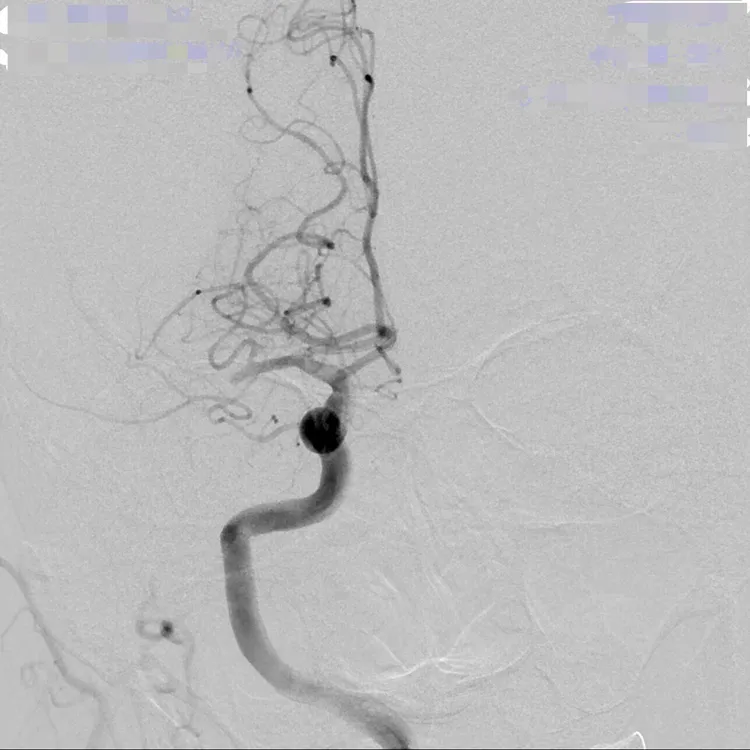

病患的血管攝影可看出,右半邊後面的血管都不見了,即血栓塞住,血流過不去。院方提供

神經放射治療科嚴寶勝副院長指出,該病患的血管攝影可看出,右半邊後面的血管都不見了,也就是血栓塞住血流過不去,影響的範圍很大,必須儘快進行顱內動脈取栓術,使用專用抽吸導管或支架,經由鼠蹊部沿主動脈一路前進至被血栓阻塞的腦部動脈血管,將血栓取出清除、打通阻塞血管,恢復腦血流通暢,即時把握治療的黃金時間,讓原先缺血的組織盡快重新獲得血液。